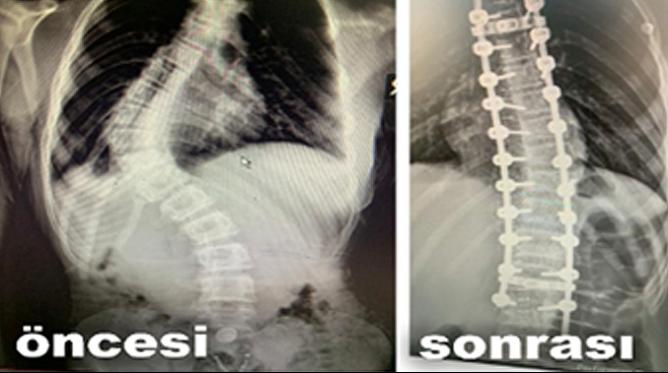

Ameliyatı gerçekleştiren Op. Dr. Sezgin Bahadır Tekin, omurga eğriliklerine ilişkin bilgiler vererek ameliyatın riskli olmasına rağmen başarılı geçtiğine vurgu yaptı. Op. Dr. Tekin, omurga eğriliklerine genç kızlarda sıkça rastlandığına dikkat çekerek, “Omurga eğrilikleri toplumun büyük bir kısmında görülen problemlerden biri. Özellikle genç kız çocuklarında omurga eğriliklerini daha sık görüyoruz. Tüm omurga eğriliklerine cerrahi operasyon yapılmıyor. İlerlemiş omurga eğriliklerine cerrahi olarak müdahale ediyoruz. Hastamız Sultan Yaşar, omurga eğriliği şikayeti ile hastanemize başvurdu. Hastamızın yaklaşık 70-75 derecelik bir eğriliği mevcuttu. Bu eğriliği büyük ve riskli bir cerrahi müdahale ile düzeltmeye karar verdik” dedi.

Ekip olarak büyük bir başarıya imza attıklarını kaydeden Op. Dr. Tekin, “Müdahale ekibimiz, anestezi ekibimizle birlikte başarılı bir operasyonu tamamladık. Omurga eğrilikleri skolyoz veya kifoz olarak, ya da ikisinin birlikte olduğu deformiteler olarak görülebilir. Hastamız Sultan’ın yalnızca skolyozu mevcuttu. Benzer hastaların ameliyatlarında bazı sıkıntılar gelişebiliyor. Omurganın içerisinden omurilik geçtiği için çokça dikkat gerektiriyor. Omurilik tüm vücudu uyaran sinirleri barındırıyor. Hastanın yürümesini, bağırsak hareketlerini sağlayan birçok sinir bu noktadan geçtiği için ameliyat esnasında sinir cihazlarını da kullandık. Cerrahi sonrasında hiçbir sorun yaşanmadı, serviste takibimizi gerçekleştiriyoruz. 2-3 gün içerisinde taburcu etmeyi düşünüyoruz” ifadelerine yer verdi. (Aslı Emektar / gaziantepdogus)